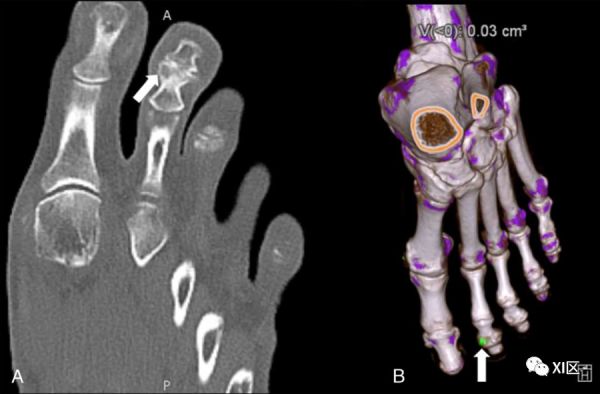

DECT的一个有趣的用途是使用多平面和3D材料分解重建来诊断痛风,类似于区分尿酸肾结石和其他肾结石成分(图6)。最近的一项荟萃分析显示,在超过2年的病程中,使用DECT检测痛风的敏感性和特异性高于超声。

图6:一名65岁多关节疼痛患者的DECT,血清尿酸持续升高。A、 痛风关节病特征的第二远端指间关节侵蚀的显示(箭头)。B、 DECT采集的材料分解3D重建,在该采集上,在同一接头上以绿色显示尿酸钠沉积物(箭头)。

在一项模拟研究中,最近区分晶体沉积类型的努力成功地将尿酸钠沉积(痛风中普遍存在)与焦磷酸钙(假性痛风中普遍出现)或羟基磷灰石钙沉积区分开来,对不同DECT分解方法的探索证明了3D虚拟单色采集在受试者足部和踝关节的体模对照研究中对尿酸钠沉积物的定量和检测中的实用性。